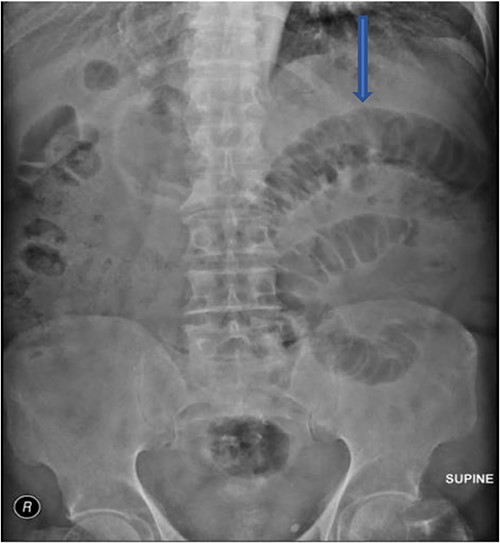

The plain film of the abdomen showed multiple air-fluid levels on the erect film (Fig. 1) and small bowel dilatation on the supine (Fig. 2). The CT showed multiple air pockets in the biliary tree, representing pneumobilia (Fig. 3). It also showed evidence of a circular radio-dense stone measuring 2 cm within the distal jejunum, leading to obstruction and dilatation of the proximal jejunum (Fig. 4).